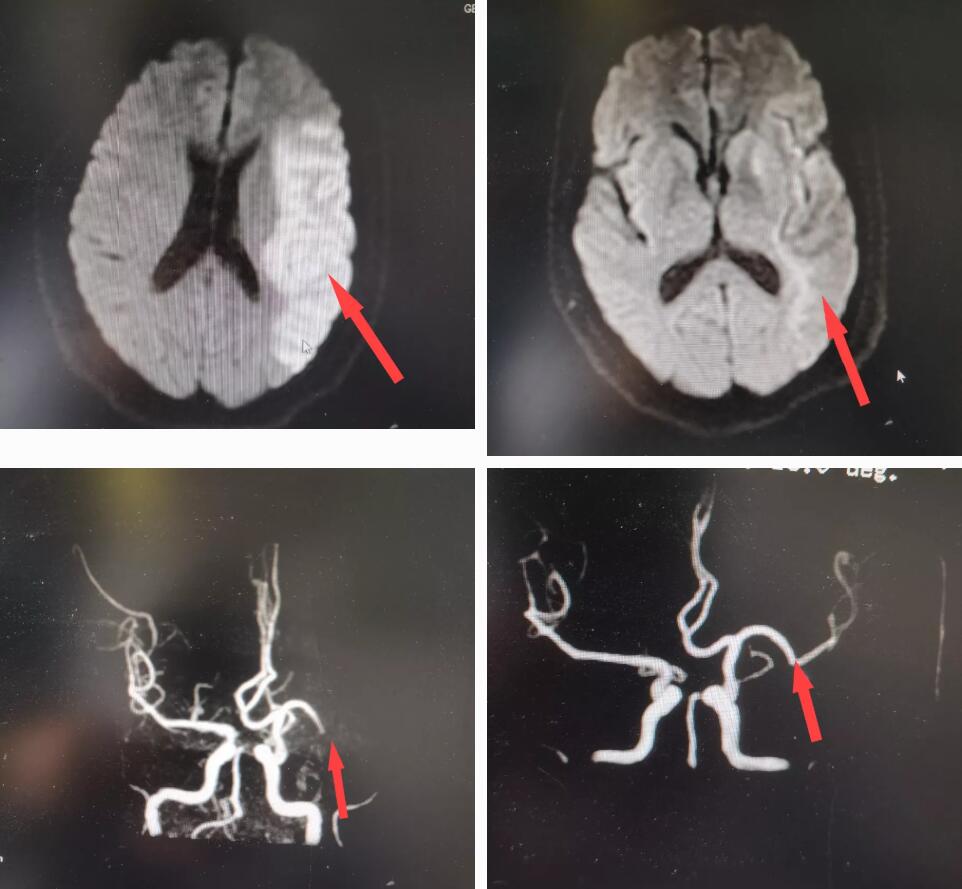

2019年8月29日,王先生在无明显诱因下出现右侧肢体无力,不能自主行走,头晕、头痛明显,伴随呕吐,被120送至我院后,经头颅MRI检查后发现,王先生是“大脑中动脉堵塞引起的急性脑梗死”导致的右侧偏瘫。

△磁共振显示中动脉堵塞(左)和溶栓后(右)

王先生有“脑梗死”病史已5年有余,这次急性脑梗死是他这么多年以来情况最危急的一次。经过急性溶栓后,王先生的情况明显好转,逐渐恢复到了正常生活。